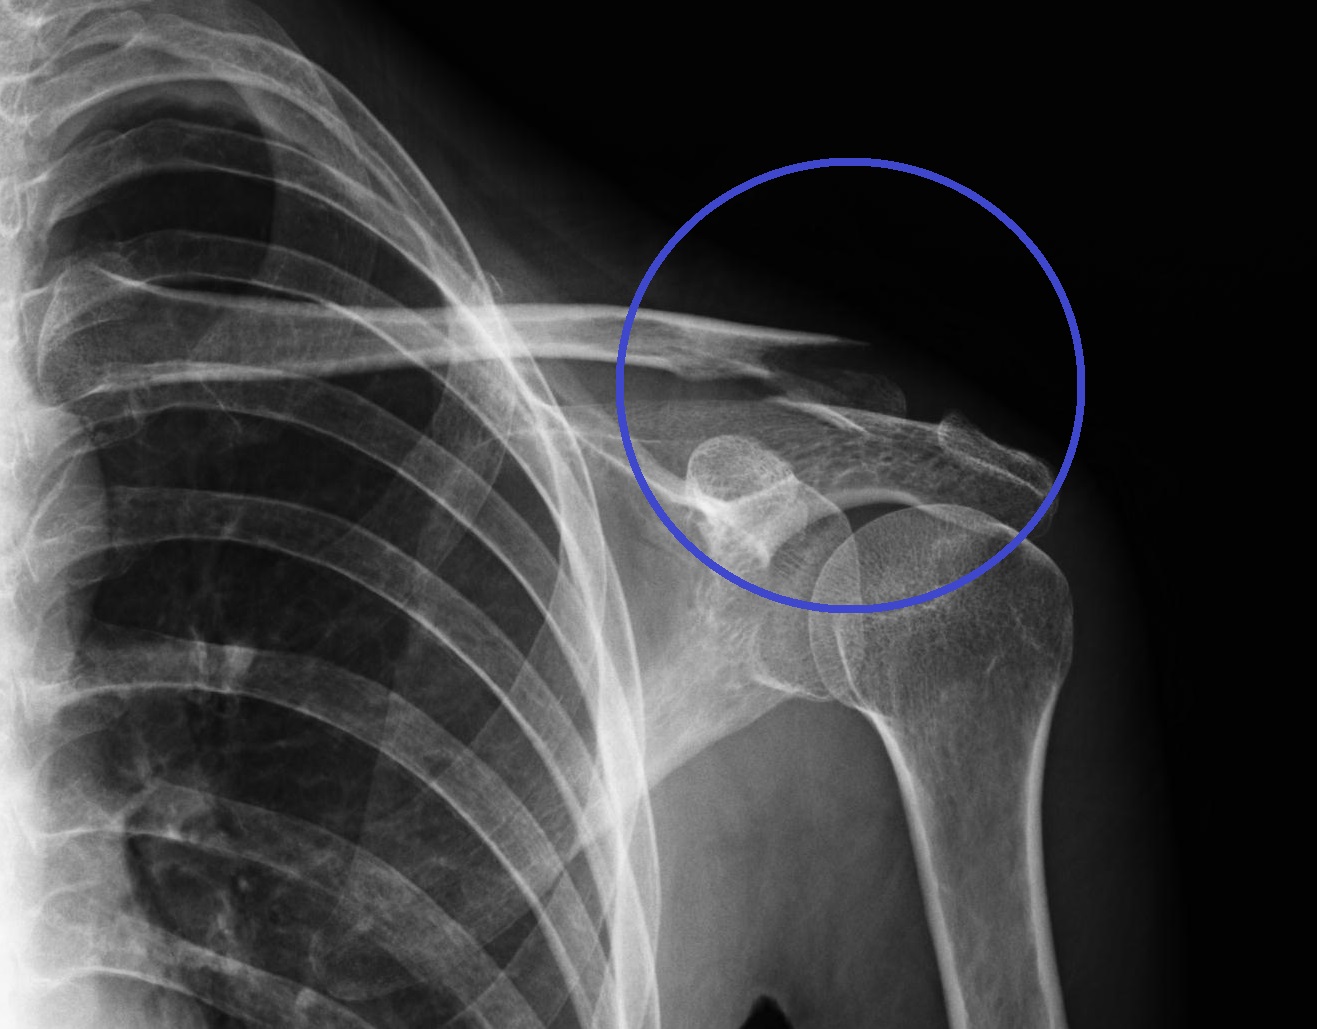

肋骨骨折のレントゲン 胸部単純レントゲンによる肋骨骨折の感度は50%程度であるとされています。 呼吸が整ってきたのは、骨折から 1分から2分経った後。 肋骨骨折の程度によっては、これが激痛で 耐えられないという人や、 痛みが強すぎてどんどん呼吸が浅くなるという人、 動くことが辛いという人がいます。